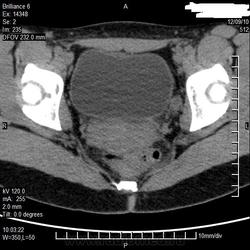

добрый вечер коллеги!друг уролог попросил проконсультировать на сайте, говорит около матки кисту подозревают. Врачи КТ у нас все разъехались, снимки остались неописаны. Может надо еще файлов закачать, я в кт ничего не понимаю))))) заранее спасибо!

КТ малого таза без подготовки кишечника и без перорального контрастирования подвздошной кишки позитивным контрастом не особо информативна, особенно натив (не введен контраст в/в). Если нет возможности сделать МРТ, то тогда понятно КТ, но для гинекологии его применяют мало. УЗИ девушке неизвестных лет, наверное, делалось?

Кистовидно измененный левый яичник, киста около 2,5 см. Хронический цистит, стенка мочевого пузыря при добротном наполнении утолщена.

яичник слева по мне нормальный. Вот справа на уровне тела матки непонятно что, как осумкованная жидкость какая-то, полистать бы серию... А с чем больная-то (анамнез?). Ну и про контраст уже сказали... Кстати, варикозного расширения вен помимо всего прочего нет тут?

25 лет, извините, что не написала, я и в вверху ошиблась-написала мужчина.

уролог говорит по задней стенке мочевого пузыря что-то. Спасибо за высказанные мнения))))))))))))))